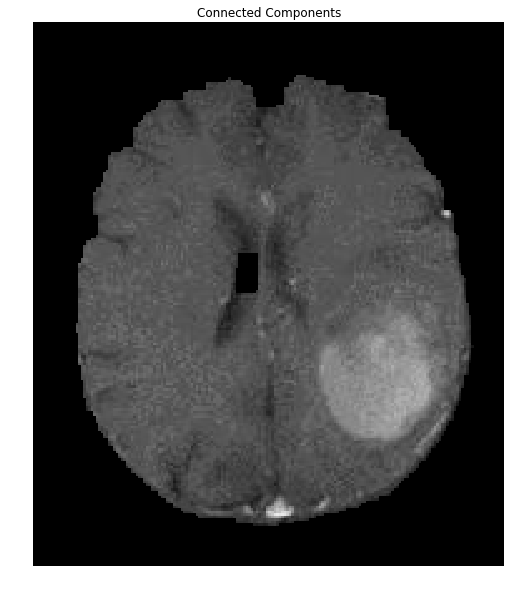

We can now extract the brain:

brain_out = img.copy()

#In a copy of the original image, clear those pixels that don't correspond to the brain

brain_out[closing==False] = (0,0,0)

ShowImage('Connected Components',brain_out,'rgb')